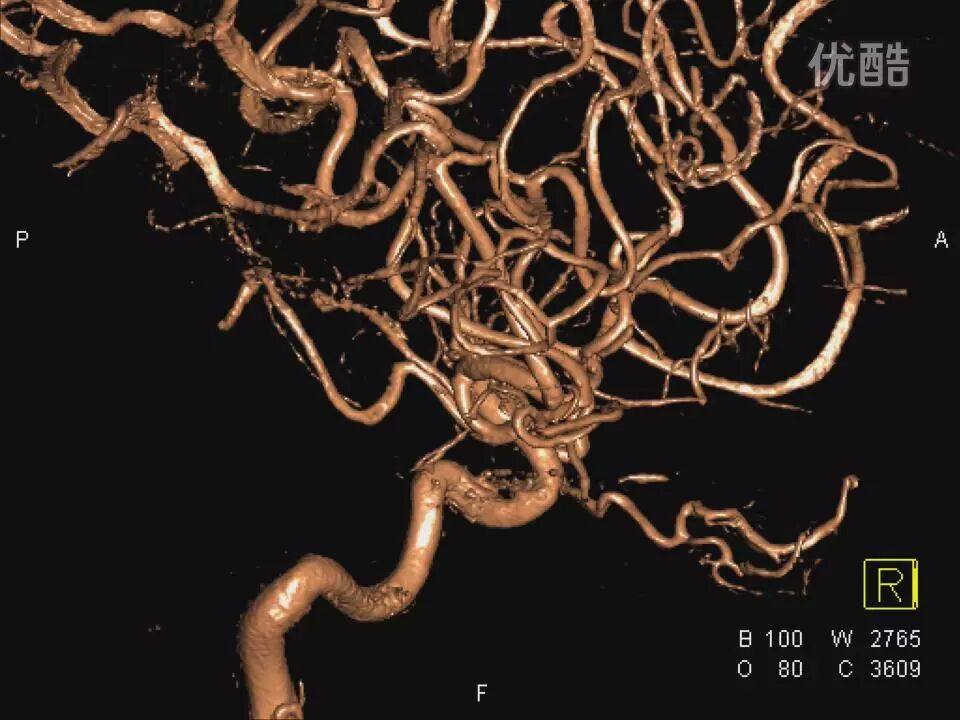

许秉权教授:显微手术钳夹海绵窦内动脉瘤